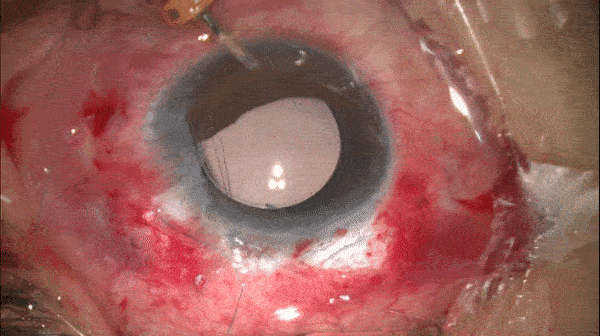

注入IOL

注入IOL并将另一侧晶体襻留置于眼外。

开睑器怎么用术说睛彩 | 金海鹰教授:使用8-0缝线的无巩膜瓣人工晶体固定手术_https://www.jmylbn.com_新闻资讯_第6张